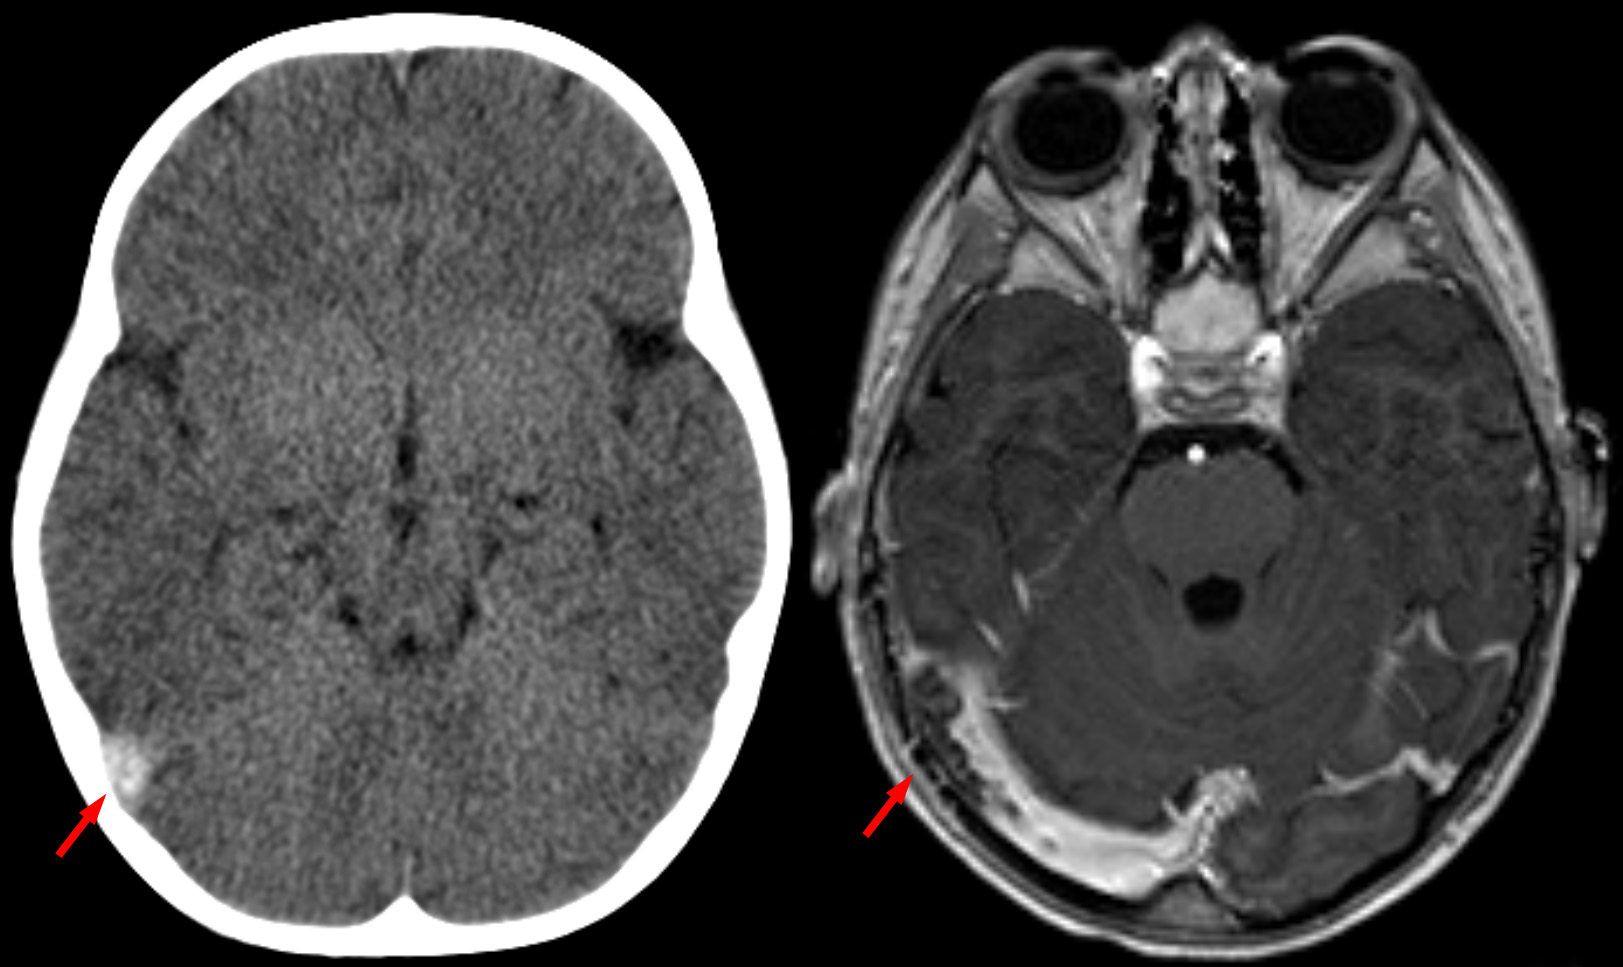

Las curvas ROC también son utilizadas para comparar la eficacia de diferentes pruebas para un diagnóstico o de una prueba en varios estadios de una enfermedad.

En la siguiente gráfica, podemos observar las diferentes posibilidades de una curva ROC. La exactitud de la prueba aumenta a medida que la curva se desplaza desde la diagonal hacia el vértice superior izquierdo. Si la discriminación fuera perfecta —100 % sensibilidad y 100 % especificidad o 1-especificidad—, pasaría por dicho punto.

Interpretación de una curva ROC, de acuerdo con la eficacia de pruebas diagnósticas [imagen]. Tomada de Burgos, M y Materola, C. (2010). “Cómo interpretar un artículo sobre pruebas diagnósticas”, p. 306.

En la siguiente gráfica, podemos observar cómo a medida que el estadio de cáncer colorrectal aumenta, también crece la sensibilidad de la prueba del antígeno carcinoembrionario como prueba diagnóstica.

Interpretación de una curva ROC, de acuerdo con los estadios de la enfermedad [imagen]. Tomada de Fletcher, R. y Fletcher, S. (2008). “Diagnóstico”, p. 47.